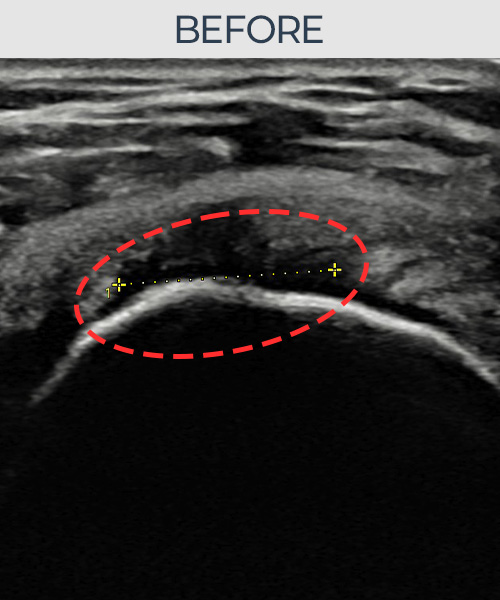

수천건의 수술 경험을 바탕으로 정확히 진단하여

인대파열을 비수술로 치료합니다.

플래티넘정형외과에서는 수술이 필요없는 인대파열만을

정확히 진단하여 특허받은 술기로 비수술로 치료합니다.